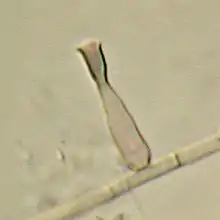

Phialophora verrucosa produces vase-shaped phialides with dark brown, cup-shaped collarettes.[7] Each phialide is typically 3–4 μm wide and 4–7 μm long.[6] Teardrop-shaped,[3] smooth-walled conidia are formed at the apices of the collarettes and accumulate in clusters. Conidia are typically 2.5–4 μm by 1.5 3 μm in size.[8] Hyphae are brown, cylindrical, and septate and are composed of thick-walled cells.[5] The hyphae do not produce conidia.[3]P. verrucosa grows well over a range of temperatures, 21–37 °C (70–99 °F) with an optimal growth temperature of 30 °C (86 °F).[9] Colonies grow slowly on oxalic acid and malt extract agar.[3] Grown on Sabouraud's agar at 3 °C (37 °F), the colony attains a diameter of 3–4 cm after 2 weeks incubation.[6]